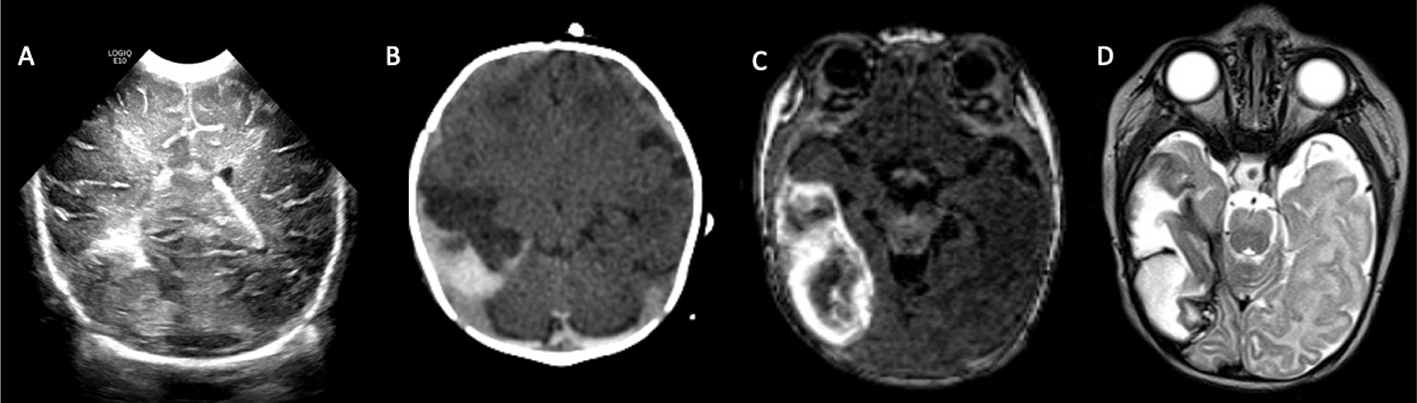

Acute phases of fetal stroke, such as in case of congenital heart disease or twin-twin transfusion syndrome (TTTS), may only rarely be detected prenatally. Fetal stroke often manifests with the chronic features of unilateral ventriculomegaly and volume loss with or without associated hemorrhage (Figures 1 and 2).

Fig 1

Figure 1. Acute and chronic fetal infarctions. 29 weeks of gestation fetus with a chronic stroke in the right hemisphere. (A) Axial HASTE (Half Fourier Singleshot Turbo Spin-Echo) and (B) Gradient Recall Echo (GRE) images showing unilateral enlargement of the right lateral ventricle, with periventricular white matter loss (white arrow) and linear blood staining (black arrowhead). 21 weeks of gestation fetus with congenital heart disease with acute stroke in the right hemisphere. (C) Axial DWI and (D) ADC map showing areas of reduced diffusion in the left ACA and MCA territories (black arrow) with questionable infarct in the right MCA territory (white arrowhead). Case courtesy of Dr. Tamara Feygin, Department of Radiology, Children’s Hospital of Philadelphia.